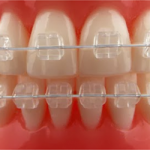

Tedavi Yöntemleri Self-Ligating Sistemler Gölcük Ortodonti Lingual Ortodonti Fonksiyonel Aparey eCligner Sistemi Ağız Dışı Apareyler Hareketli Apareyler Gömülü Kanin Dişi Tedavisi